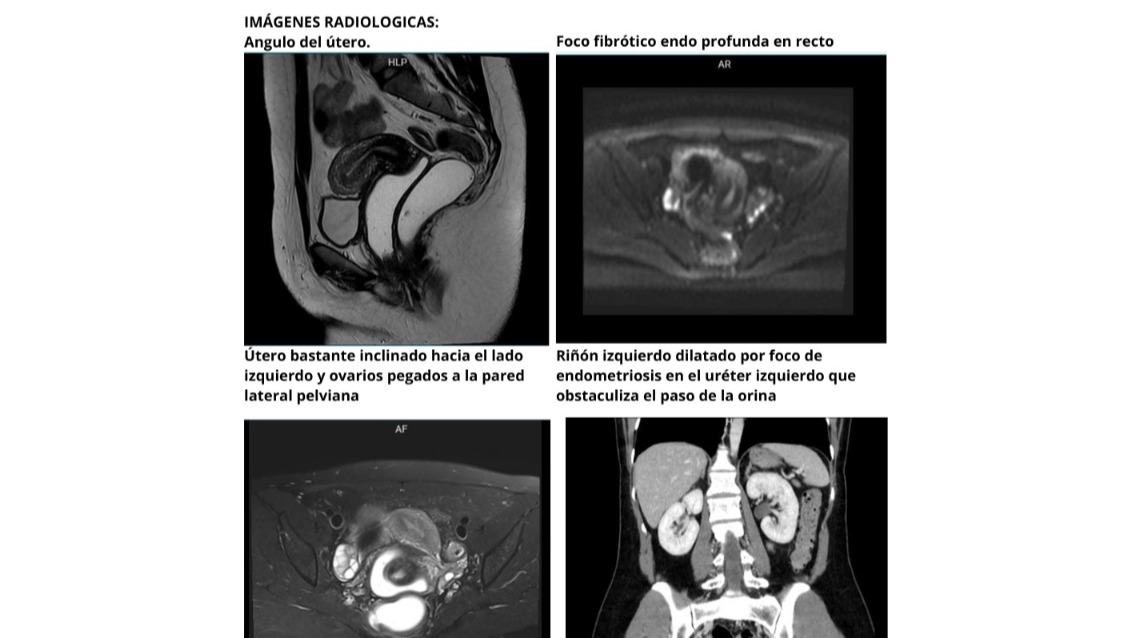

- Útero: Está desplazado, lo que dificulta el embarazo y causa molestias constantes.

- Ovarios: Están adheridos a la pared pélvica, afectando mi fertilidad y generando un dolor crónico.

- Intestino: Tiene lesiones profundas que me provocan dolor al defecar y problemas digestivos.

- Vejiga: Siento molestias cada vez que orino.